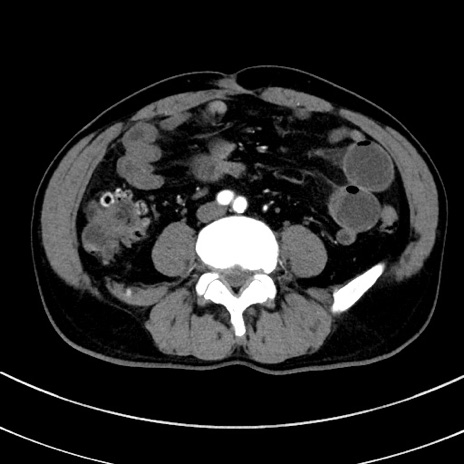

症例8(横断像)

【症例】 60歳代男性

【主訴】 黒色吐物

【現病歴】 4日前から嘔気自覚、2日前の朝食後にも嘔気あり、自分で手で嘔吐反射起こし嘔吐したところ血が混ざっていたため受診。

【既往歴】 5年前汎発性腹膜炎を伴う急性虫垂炎で手術、高血圧、前立腺肥大症、高脂血症

【身体所見】 腹部正中に手術癩痕あり 腹部平坦・軟圧痛なし膨満感あり

【データ】WBC 8400、CRP 4.54